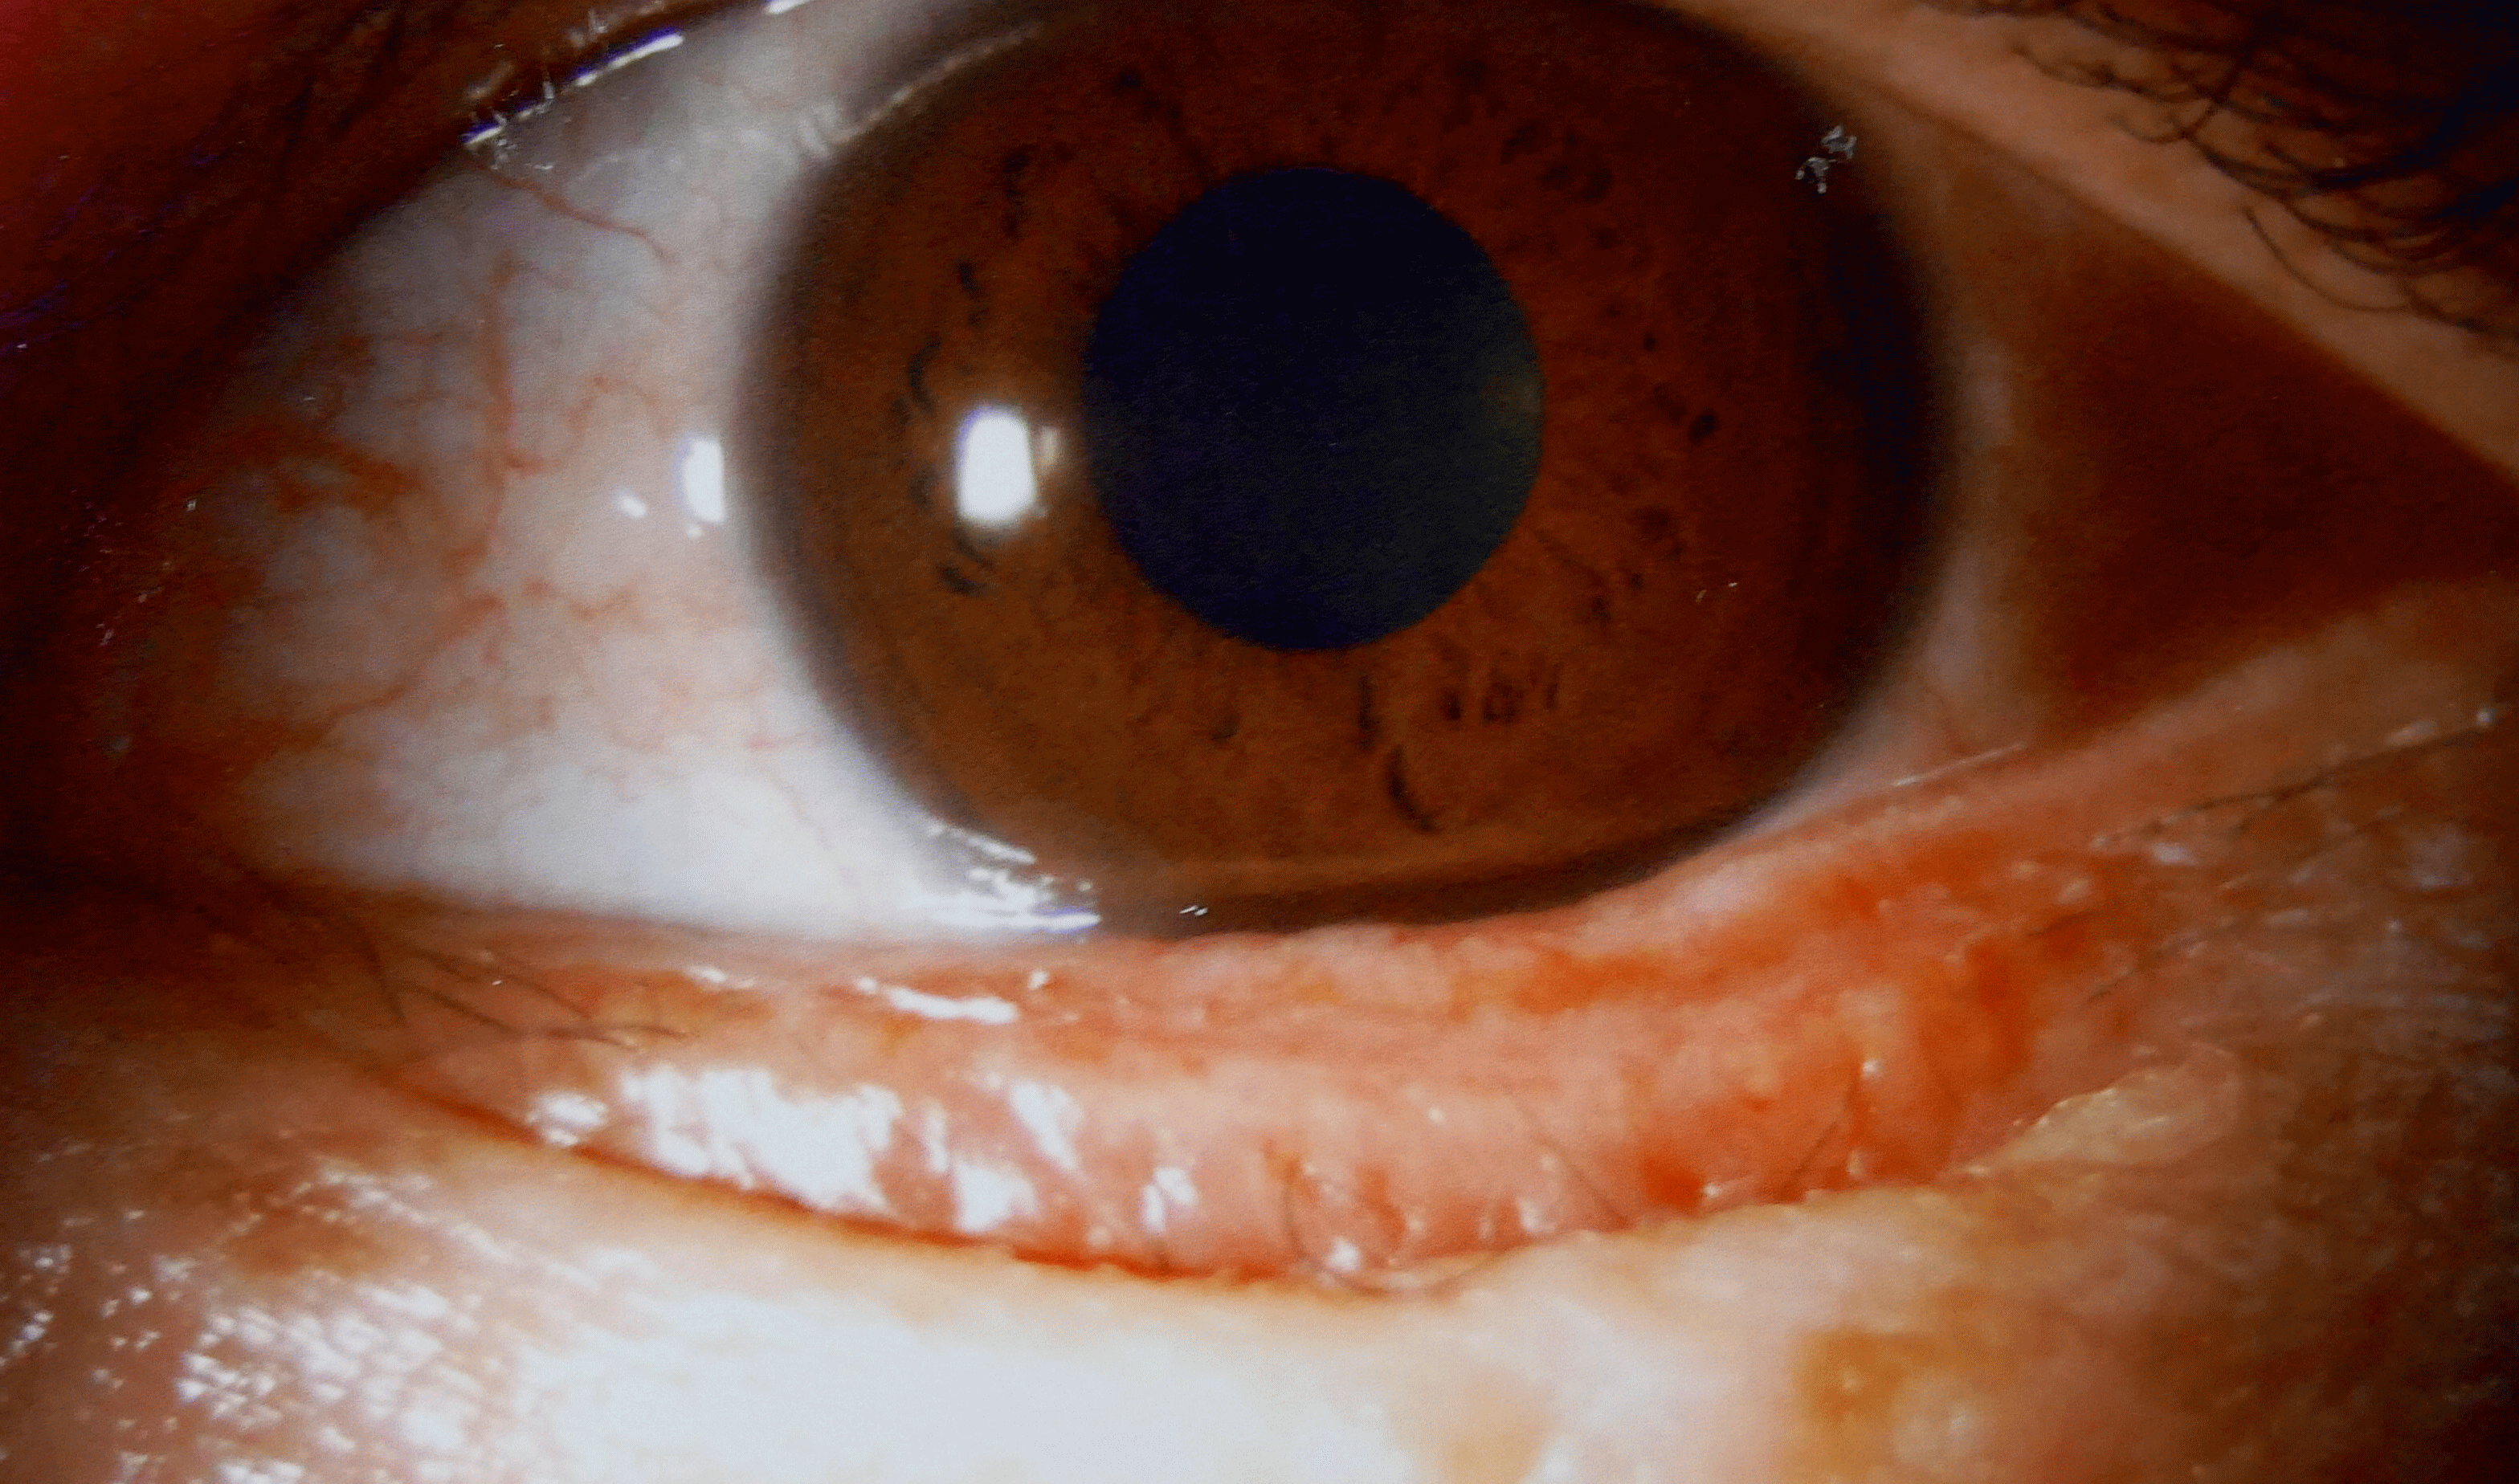

下は数年前に逆さマツゲの手術をした方です。最近またごろごろするとのことでした。

左写真のように下のマツゲが目に当たっています。手術は左図のようにマツゲと毛根を一緒

に赤い部分を切り取ります。毛根が残っていたらレーザーで焼却します。右写真は手術直後

です。